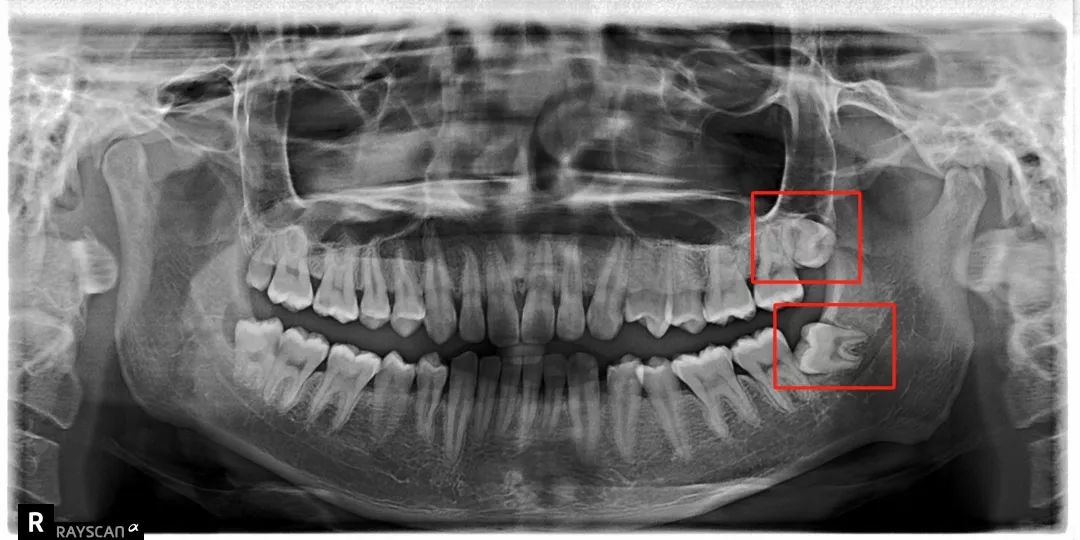

科普一波智齿~

把整副牙齿挤歪:

比方说像树根一样长出很多「根」

扎根在骨头里,死死抓住

还有一部分智齿长期发炎

可能会跟我们的骨头黏连